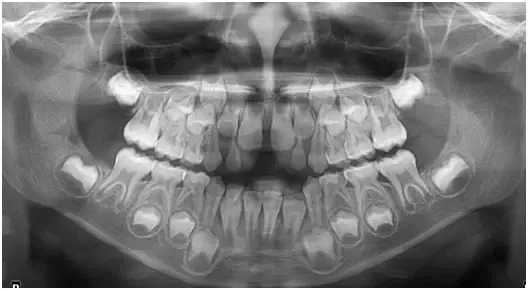

03、口腔全景片

检查儿童多生牙

正常人会长28-32颗恒牙

超过了32颗多长出来的恒牙叫“多生牙”

“多生牙”不仅会占不属于它的位置

有时还赖在“窝”里不肯出来

让其他恒牙无法正常萌出、造成牙列不齐等

有时多生牙隐蔽得很好,表面看不出来

因此一定要带孩子拍片检查